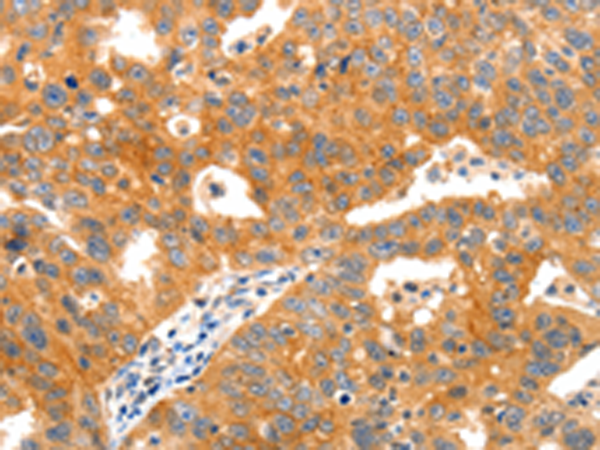

分类: 科研抗体货号: P11004别名: LIG1; LIG-1应用: WB,IHC反应种属: Human, Mouse